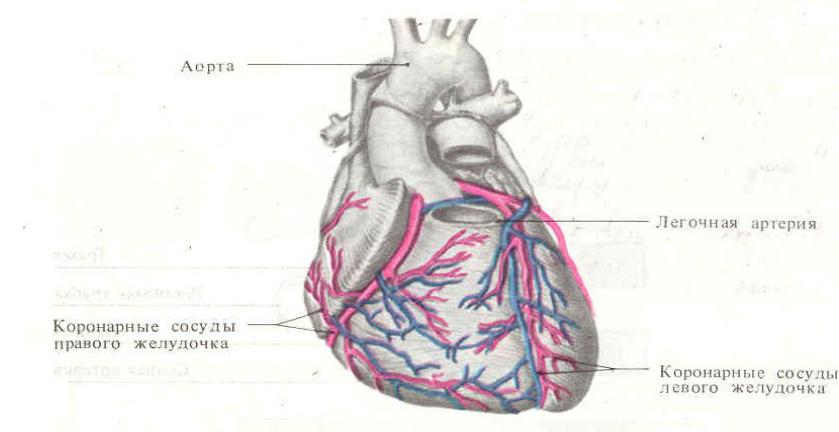

Анатомия коронарных артерий: КТ-изображения